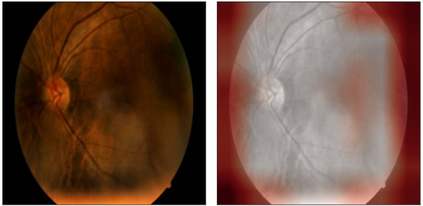

Glaucoma is one of the most severe eye diseases, characterized by rapid progression and leading to irreversible blindness. It is often the case that pathology diagnostics is carried out when the one's sight has already significantly degraded due to the lack of noticeable symptoms at early stage of the disease. Regular glaucoma screenings of the population shall improve early-stage detection, however the desirable frequency of etymological checkups is often not feasible due to excessive load imposed by manual diagnostics on limited number of specialists. Considering the basic methodology to detect glaucoma is to analyze fundus images for the \textit{optic-disc-to-optic-cup ratio}, Machine Learning domain can offer sophisticated tooling for image processing and classification. In our work, we propose an advanced image pre-processing technique combined with an ensemble of deep classification networks. Our \textit{Retinal Auto Detection (RADNet)} model has been successfully tested on Rotterdam EyePACS AIROGS train dataset with AUC of 0.92, and then additionally finetuned and tested on a fraction of RIM-ONE DL dataset with AUC of 0.91.